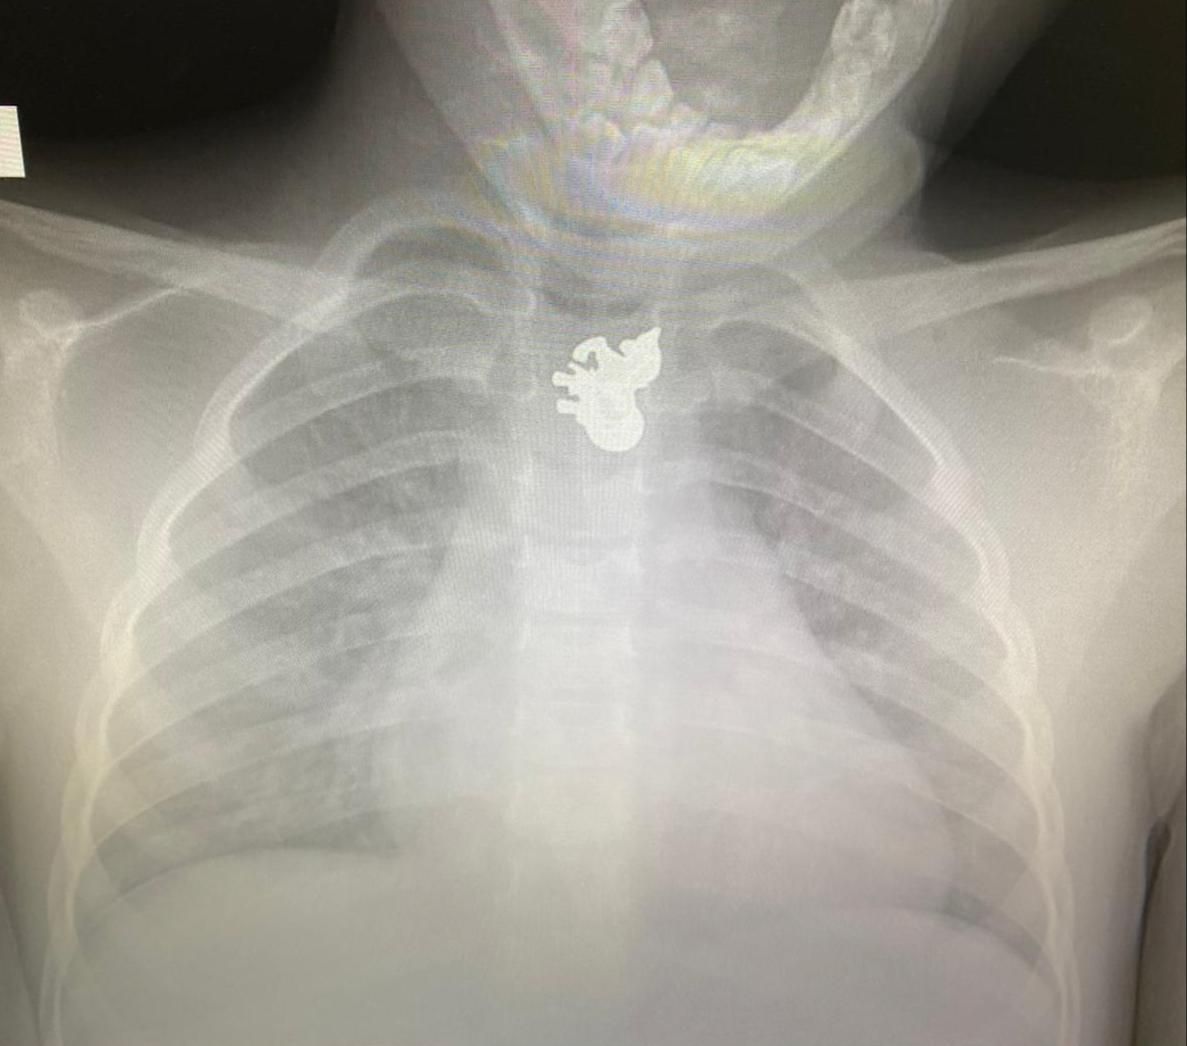

ד"ר סמדר מנהיים, הרופאה שטיפלה בילדה עם הגעתה, מדווחת: "הבדיקה הראשונית בשילוב עם צילום רנטגן שערכנו הראו שהתליון לא נמצא בקנה הנשימה, ולכן אין חשש מיידי לחנק. יחד עם זאת, מהצילום לא היה ברור האם החפץ מכיל קצוות חדים, אשר עלול לגרום לנזק לוושט, ולכן קראנו מיידית למומחית גסטרו לטיפול במקרה".

ד"ר מיכל קורי, מנהלת אשפוז יום ילדים וגסטרו במרכז הרפואי קפלן, הסבירה: "צילום הרנטגן שעשינו לילדה העלה בבירור כי התליון נתקע בוושט, מה שקורה לא אחת אצל ילדים שבולעים חפצים או חלקי משחקים. חששנו שאולי יש לתליון קצוות חדים, שעלולים לפגוע בוושט, ועל כן הבהלנו אותה לחדר הניתוח על מנת לבצע בה גסטרוסקופיה דחופה תחת הרדמה כללית. במקרה המדובר, שמחנו לראות שלא נגרם לילדה נזק נוסף לוושט".